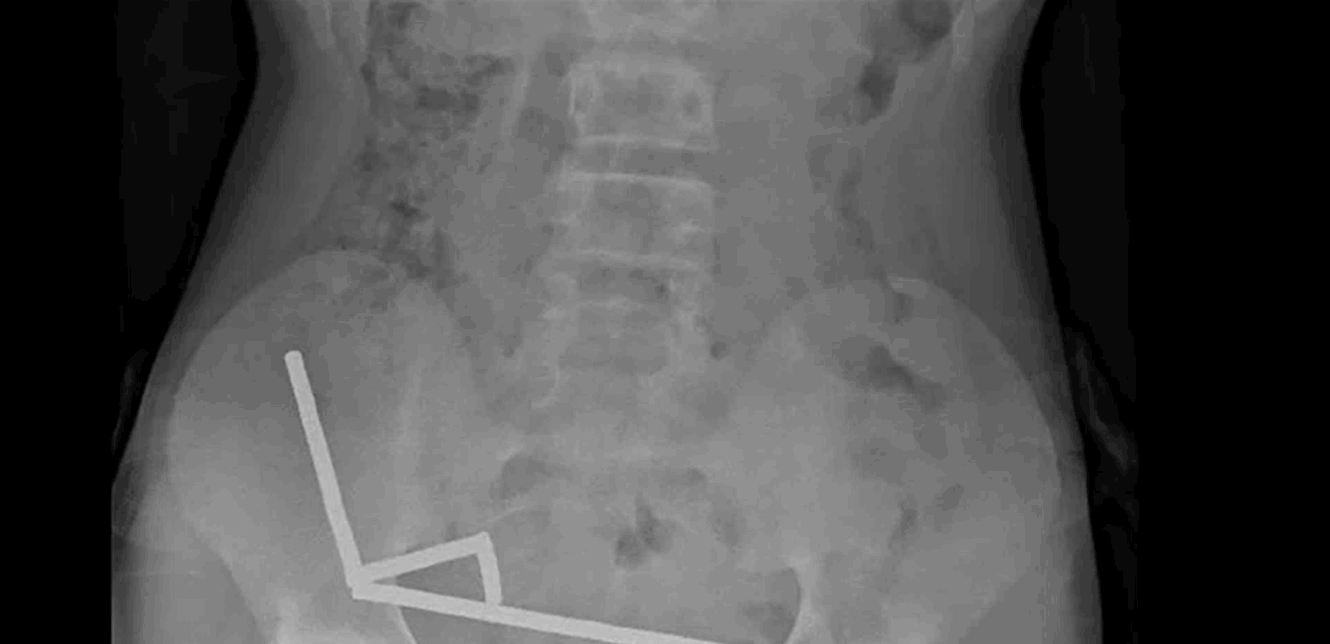

وقال التقرير أن الطفل “أكد أنه ابتلع ما يقرب من 80-100 مغناطيس عالي الطاقة (نيوديميوم) بأبعاد 5x2 مم قبل حوالي أسبوع“. وأضافوا أن المغناطيسات، التي حُظرت في نيوزيلندا منذ يناير 2013، تم شراؤها من منصة التسوق الإلكترونية تيمو. وأظهرت الأشعة السينية أن المغناطيسات قد تكتلت معًا في أربعة خطوط مستقيمة داخل أمعاء الطفل.

وشرح التقرير: “يبدو أن هذه المغناطيسات كانت في أجزاء منفصلة من الأمعاء ملتصقة ببعضها البعض بسبب القوى المغناطيسية“. كما أفاد الأطباء بأن ضغط المغناطيس تسبب في نخر (موت الأنسجة) في أربع مناطق من الأمعاء الدقيقة والأعور (جزء من الأمعاء الغليظة) للصبي.